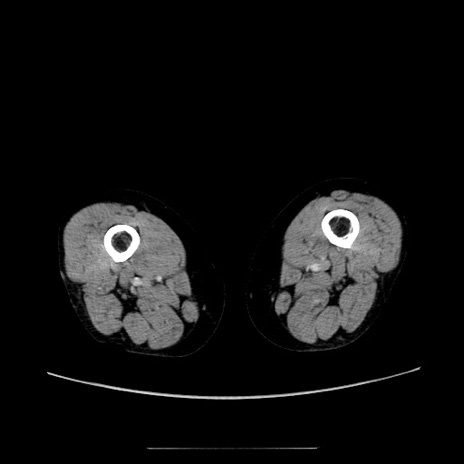

症例5(横断像)

【症例】70歳代女性

【主訴】お腹が張る

【現病歴】1週間くらい前から腹部膨満の自覚あり。昨日夜から増悪したため、本日救急外来受診。

【身体所見】意識清明、BT 36.5℃、BP 165/106mmHg、HR 80bpm、SpO2 98%、腹部:膨満、軟、自発痛・圧痛なし、触診にて不快感あり、腸蠕動音:減弱

【データ】WBC 12600、CRP 1.04